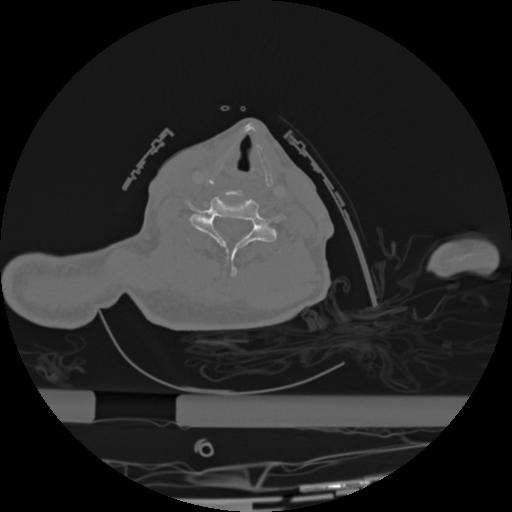

22 ANGIO,CE,Vol,0.5,ANGIO,,